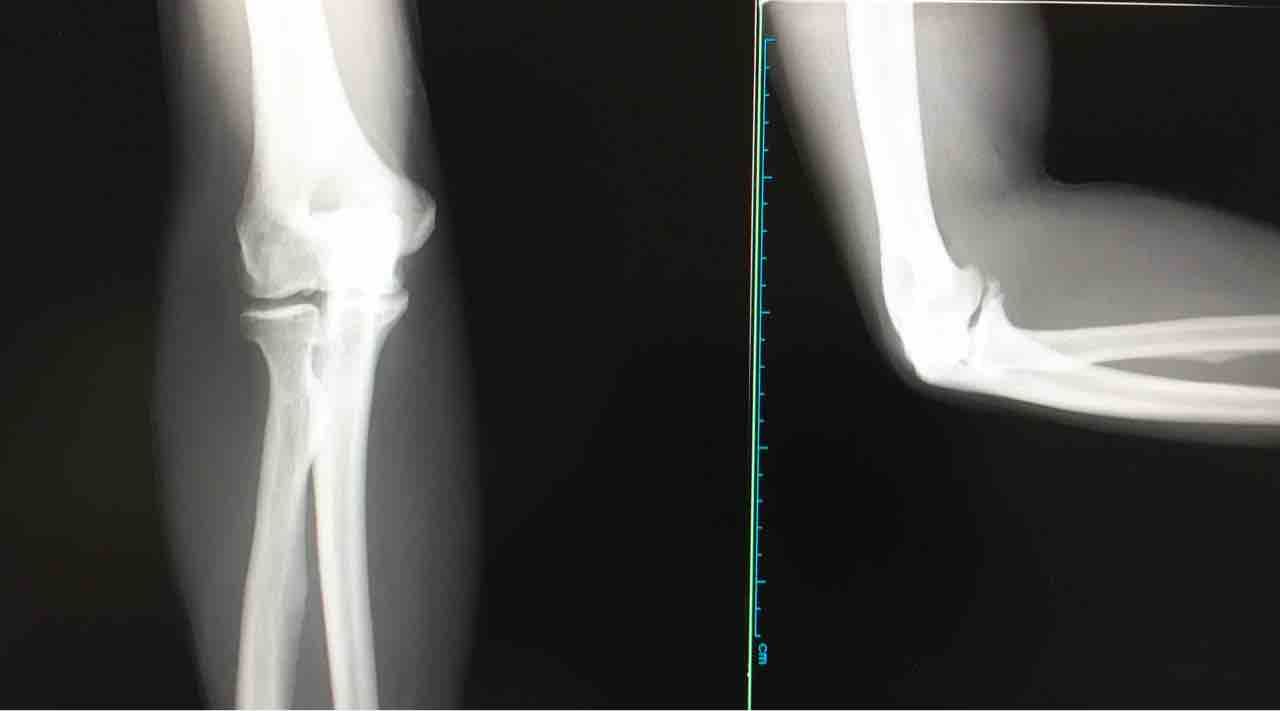

20185月29 黄金の右(笑) 肘周辺が炎症。長年、酷使してるからねー(^^;。一部変形しているものの骨には異常なし。注射して飲み薬、貼り薬をもらった^_^v。メガで鍛えすぎたな(笑)。ストレッチをするようアドバイスを受けた。たしかに前腕はやってないね。また、伸び代発見♪(笑)。 「日記」カテゴリの最新記事 コメント コメントフォーム 名前 コメント 評価する リセット リセット 顔 星 投稿する 情報を記憶